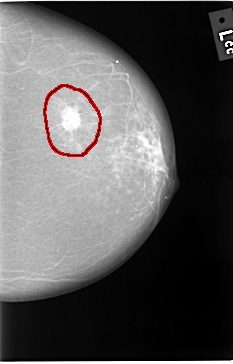

C_0037_1.RIGHT_MLO

FILE: C_0037_1.LEFT_MLO.OVERLAY

TOTAL_ABNORMALITIES 1

ABNORMALITY 1

LESION_TYPE MASS SHAPE IRREGULAR MARGINS SPICULATED

ASSESSMENT 5

SUBTLETY 5

PATHOLOGY MALIGNANT

TOTAL_OUTLINES 1

BOUNDARY